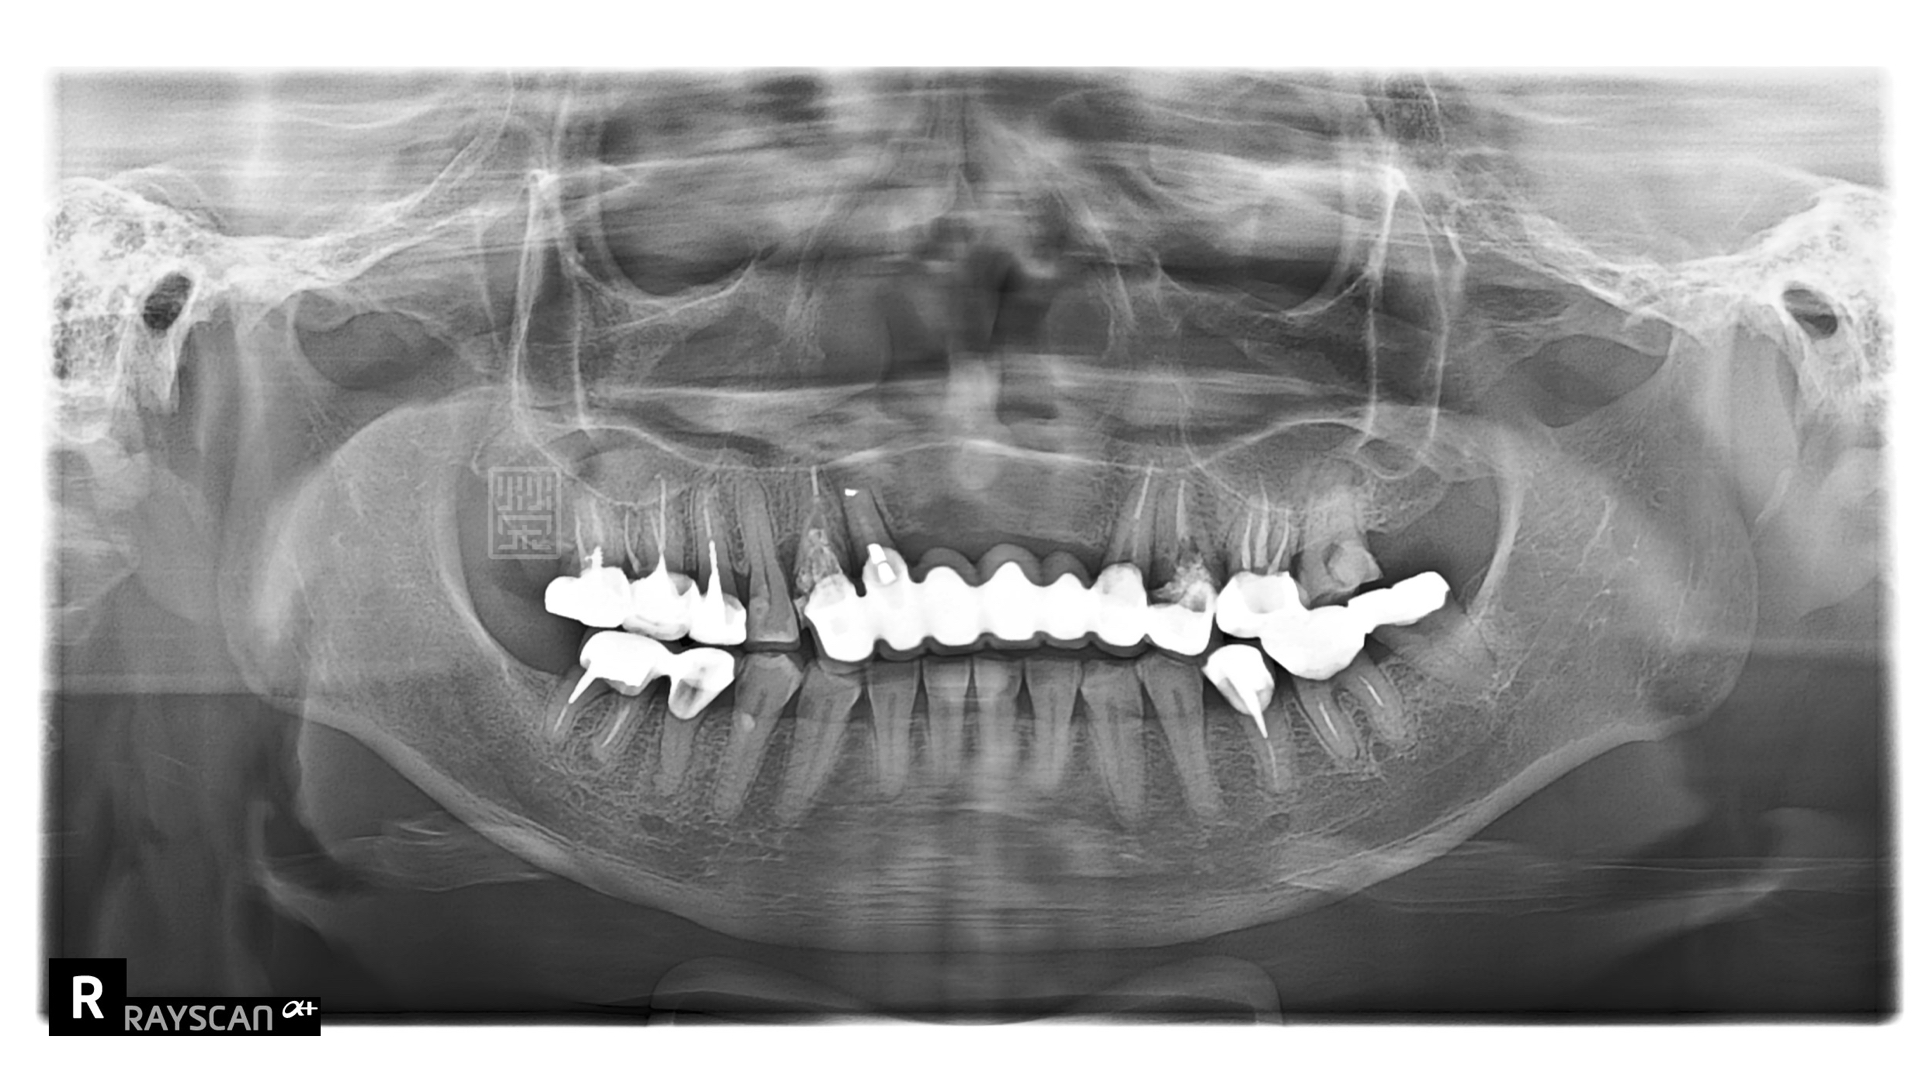

X光片中可以看到,多顆牙齒牙根蛀牙斷裂,牙套周圍二次蛀牙,根尖發炎

X光檢查下,全瓷贋復物與牙齒秘貼性良好,讓清潔容易好維持